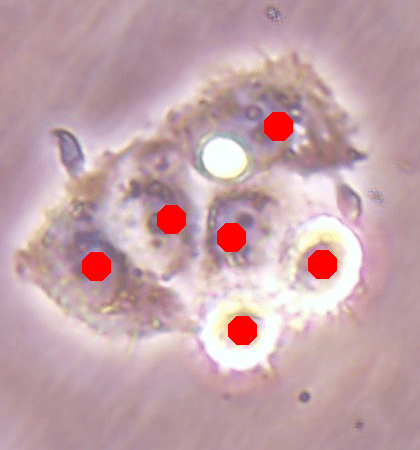

![]() |

| (a) | (b) | (c) | (d) |

For the independent test samples given in Fig. 4, Fig. 6a shows the maps of the calculated inner distances when the ground truths are given. Figs. 6b, 6c, and 6d illustrate the inner distance maps estimated by the SingleInner method, the proposed DeepDistance model, and its extended version, respectively. SingleInner learns its map as a single-task whereas our models define auxiliary tasks and learn the inner distance map in parallel to these auxiliary tasks, forcing them to learn shared representations with a shared encoder path. The latter type of learning, which is an example of multi-task learning, is known to be effective for increasing the performance of individual tasks for many domains. We also observe this performance increase in the estimated maps given in Fig. 6. SingleInner cannot successfully detect the three cells shown inside red ellipses since it cannot produce sharp enough bright regions (with distinct enough estimated distances) for these cells. Although DeepDistance, which uses one auxiliary task, leads to brighter regions for these cells, they are still not sharp enough for two of them to be identified as regional maxima. The extended version of DeepDistance, which uses one more auxiliary task, does better job in inner distance estimations such that they have sharp enough bright regions for all of these three cells.

In this figure, it is worth to noting two points: First, all methods apply the h-maxima transform on their estimated maps beforehand to suppress noise, and hence, to prevent over-segmentations and false positives. If it was not applied, SingleInner might give regional maxima for some of the three cells even though the distances estimated for their centers were not that distinct (bright). However, that case would also give many over-segmented cells and false positives. Second, none of the methods identify the cell shown inside a blue ellipse although their estimated distances yield bright regions for this cell. It is due to the evaluation method, which matches an annotated marker and a detected cell based on the distance between them since a test set image does not have boundary annotations but just a dot on each cell. In our experiments, a distance threshold is set to 30, considering image resolutions and the average cell size. This threshold may give a few incorrect matchings especially for larger cells, (e.g., the cell shown inside the blue ellipse). Increasing this threshold solves the problem for this particular cell, but this time, it will result in many incorrect matchings of detected cells with distant markers (or vice versa).